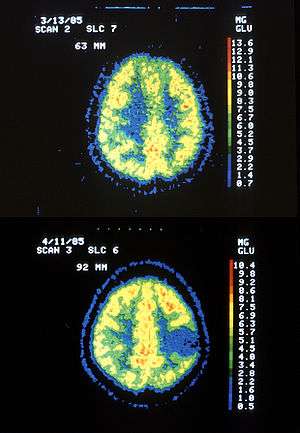

Two PET images — the upper of which shows a normal brain and the lower shows astrocytoma. | |